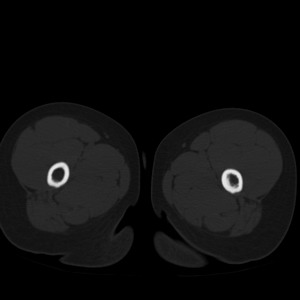

标题: PED1884:患者,男性,7岁。因右髋疼痛5天,而来院检查。 [打印本页]

标题: PED1884:患者,男性,7岁。因右髋疼痛5天,而来院检查。

因右髋疼痛5天,而来院检查。

我们考虑:1、骨皮质增厚症。2、畸形性骨炎。3、骨纤。

右髋疼痛,左侧病变,看来无症状。

支持左股骨上段骨纤维异常增殖症可能性大.